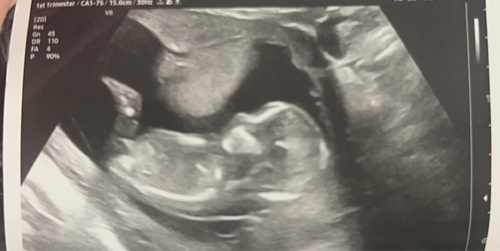

Wat ze hebben gezien op de echo:

- volledige AVSD hartafwijking

- verdikte nekplooi van 4,7mm

- vocht in hoofd tot en met de oksel

- 2 cystus in de hals

- vergrote nierbekken

- grote teen wijkt flink af van de andere tenen

En ik ben op dit moment 17 weken zwanger.. de kans is groot dat er alleen maar nog meer afwijkingen bij komen die ze nu nog niet kunnen zien..